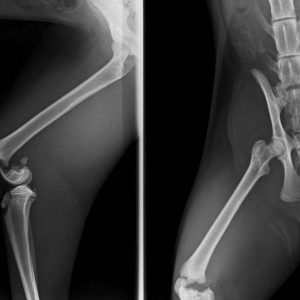

Jimmys Röntgenbild zeigte einen komplizierten Bruch im Knie. Die Tierklinik kastrierte ihn und empfahl, dass Bein zu amputieren, da die Kosten für eine OP zur Rettung des Beins sehr hoch sein würden.

Aus Erfahrung konnten wir anhand der Röntgenbilder und des Zustands des Beines den Tierfreunden schnell die Angst vor einer Amputation nehmen, denn Jimmy hat mit einer OP sehr gute Chancen, wieder gesund zu werden! ![]()

Heute morgen wurde Jimmy lange operiert und konnte heute Nachmittag wieder abgeholt werden. Sein Bruch wurde mit zwei Stiften gerichtet und ist nun wieder stabil. Er wird sehr wahrscheinlich später keinerlei Einschränkungen haben. ![]()

In sechs Wochen steht eine Röntgenkontrolle zur Nachuntersuchung an. Dabei wird sich dann auch entscheiden, ob beide Stifte drin bleiben, oder ob einer entfernt werden muss.